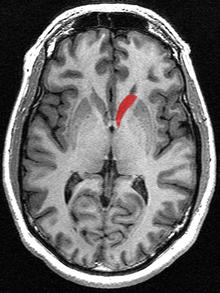

This is a transverse view of the caudate nucleus from a structural MR image.

Transverse view of the caudate nucleus from a structural MR image

The head and body of the caudate nucleus form part of the floor of the anterior horn of the lateral ventricle. After the body travels briefly towards the back of the head, the tail curves back toward the anterior, forming the roof of the inferior horn of the lateral ventricle. This means that a coronal (on a plane parallel to the face) section that cuts through the tail will also cross the body and head of the caudate nucleus.